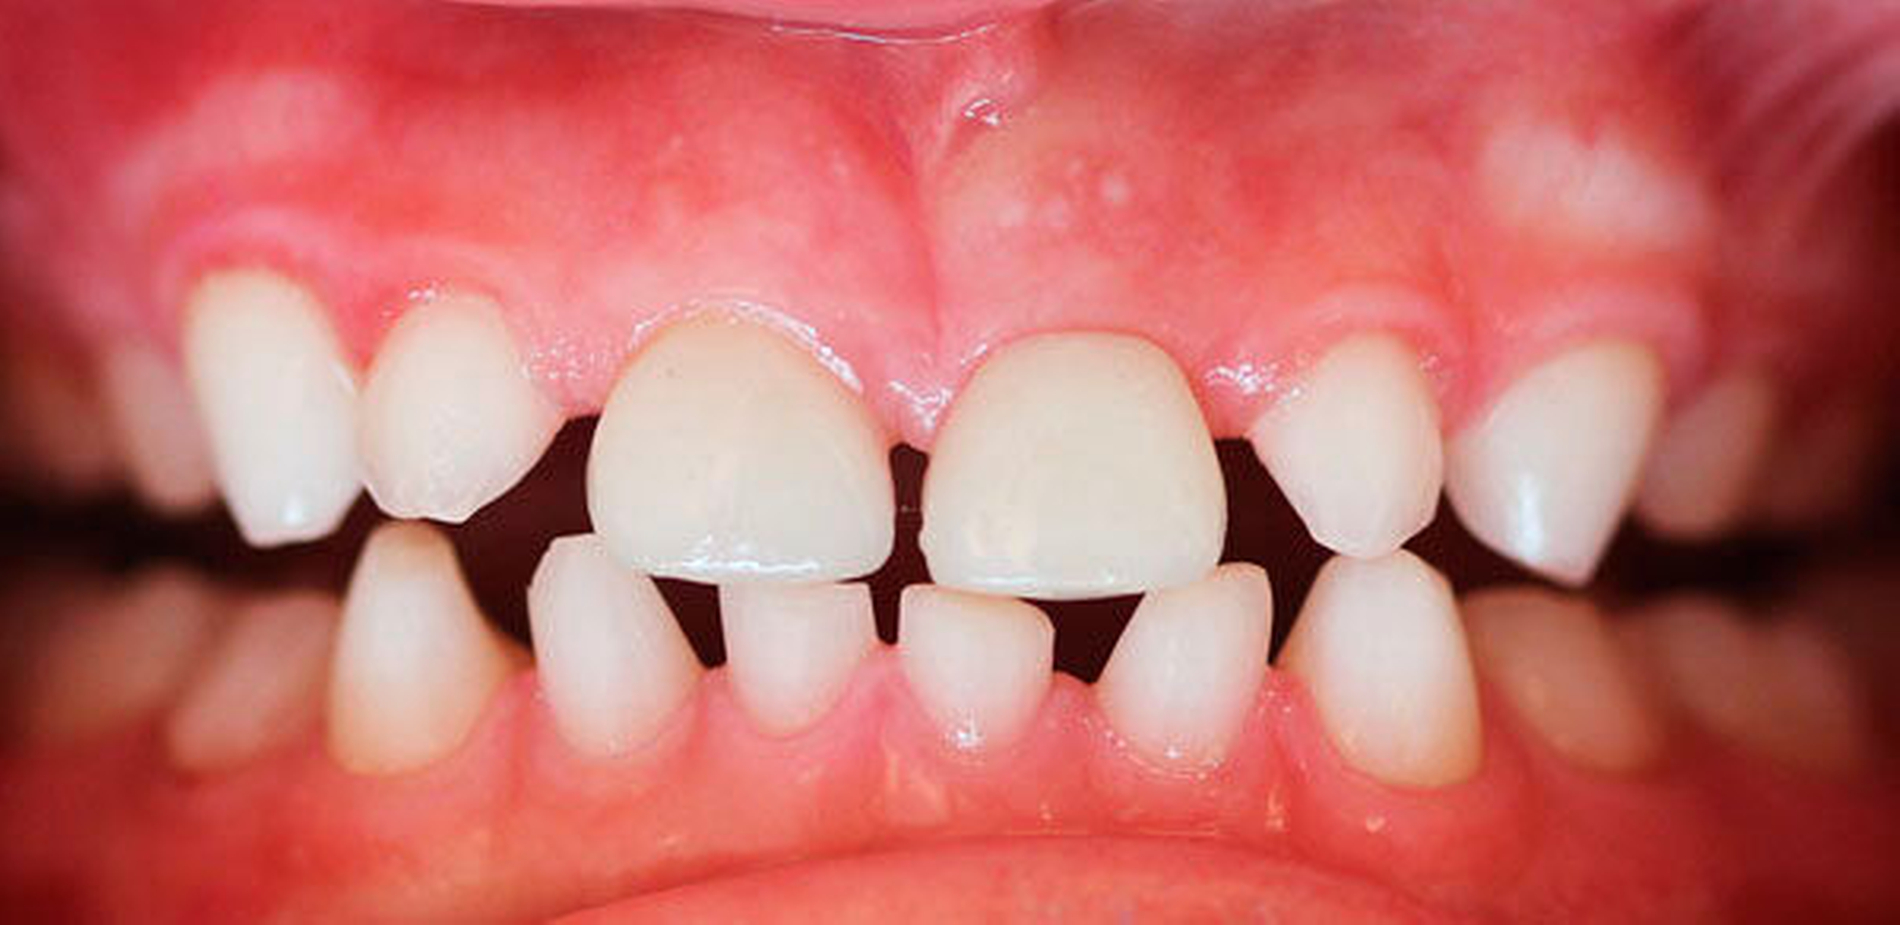

Im Februar 2018 wurden die beiden Kronen zunächst als Wachskäppchen anprobiert. Nach Fertigstellung wurden die beiden Vollkeramikkronen einzementiert (Abbildungen 4 und 5). Die Krone für Zahn 21 umschließt diesen – aufgrund der geringfügig palatinalen Position des Zahnes – auf der lingualen Seite nicht komplett, da es ansonsten zu Störkontakten an der Krone in Okklusion mit der UK-Front gekommen wäre (Abbildung 6). Dieser – bei der herkömmlichen Kronenpräparation äußerst unerwünschte Effekt – kann hier vernachlässigt werden, da die Zähne nicht beschliffen wurden. Die Kronen wurden nach Konditionierung mit Phosphorsäure mit einem adhäsiven Befestigungszement (RelyX Unicem Automix, Espe, Seefeld) eingegliedert.

Beim Blick in den Spiegel nach Einsetzen der Krone strahlte das Mädchen voller Stolz. Mit den Eltern und dem behandelnden Arzt in der Humangenetik haben wir eine abwartende Haltung bezüglich des weiteren Zahnwechsels besprochen. Die Frontzähne sind erst einmal im Bezug auf die Ästhetik und die Phonetik zufriedenstellend versorgt, die Abbeißfunktion ist gewährleistet. Später, wenn das Kind älter wird und mehr bleibende Zähne vorhanden sind, können die Kronen durch andere Kronen, die in der Morphologie bleibenden Zähnen entsprechen, ersetzt werden. Die Eltern stellten sich zunächst nach drei Wochen, dann nach fünf Monaten bei uns in der Praxis vor. Aus dem einst etwas zurückhaltenden Mädchen ist mit den neuen Zähnen ein selbstbewusstes, lächelndes Kind geworden. Sowohl die Eltern als auch das Mädchen zeigten bei den Wiedervorstellungen eine große Dankbarkeit sowohl bezüglich der Diagnosestellung – die letztlich durch uns initiiert wurde – als auch bezüglich der prothetischen Versorgung.